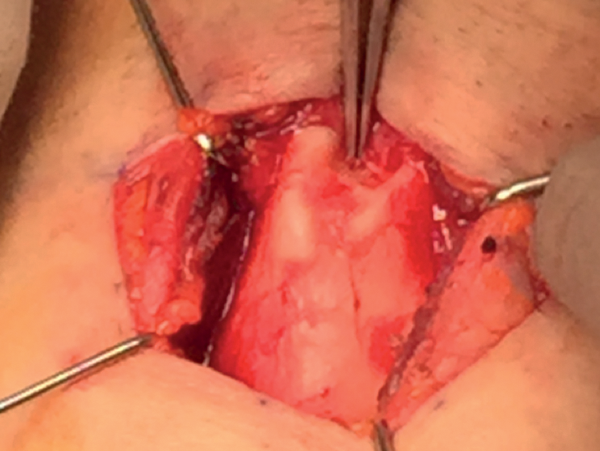

Exposure of thyroid laminae

Carefully separate the strap muscles in the midline. Meticulous haemostasis is necessary. Expose the two thyroid laminae from the notch superiorly down to the lower border of the thyroid lamina inferiorly. Put a 3/0 nylon through each side of the thyroid notch as stay suture for retraction (Figure 8).

Figure 8: top) Exposure of thyroid laminae, bottom) retraction suturing.